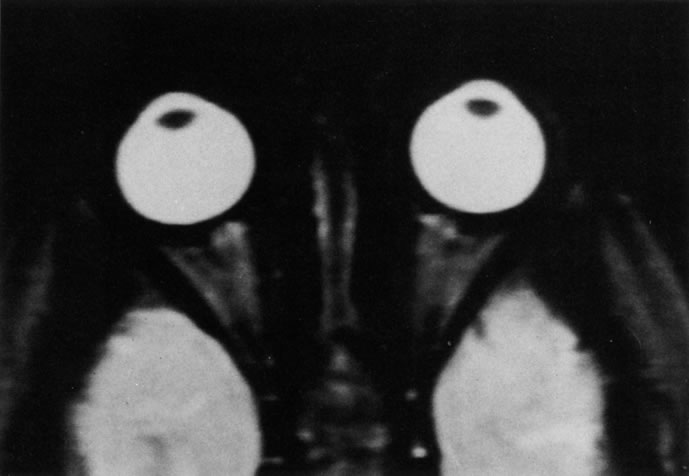

T2 RELAXATION TIME.

Application of a 90° RF pulse brings the excited nuclei into phase so that the net vector of their magnetic moments is directed perpendicular to the static magnetic field. Shortly thereafter, the magnetic moments of the nuclei spread out and point in different directions, leading to a loss of phase coherence and a resultant decay in signal intensity amplitude. The T2, or spin-spin relaxation time, is the rate of decrease in the signal of these excited nuclei as a result of the interaction and transfer of energy to unexcited adjacent nuclei. T2 ranges from a few milliseconds to a few hundred milliseconds and, for a given tissue, is always less than the Tl relaxation time. T2-weighted orbital images are easily recognized by a high-intensity signal from the vitreous (Fig. 9).5,8,16

Fig. 9. T2-weighted image of the orbits does not delineate normal anatomic details well. The lens can be visualized in the bright vitreous. (Dortzbach RK, Kronish JW, Gentry LR: Magnetic resonance imaging of the orbit. Part II. Clinical applications. Ophthal Plast Reconstr Surg 5:161, 1989)